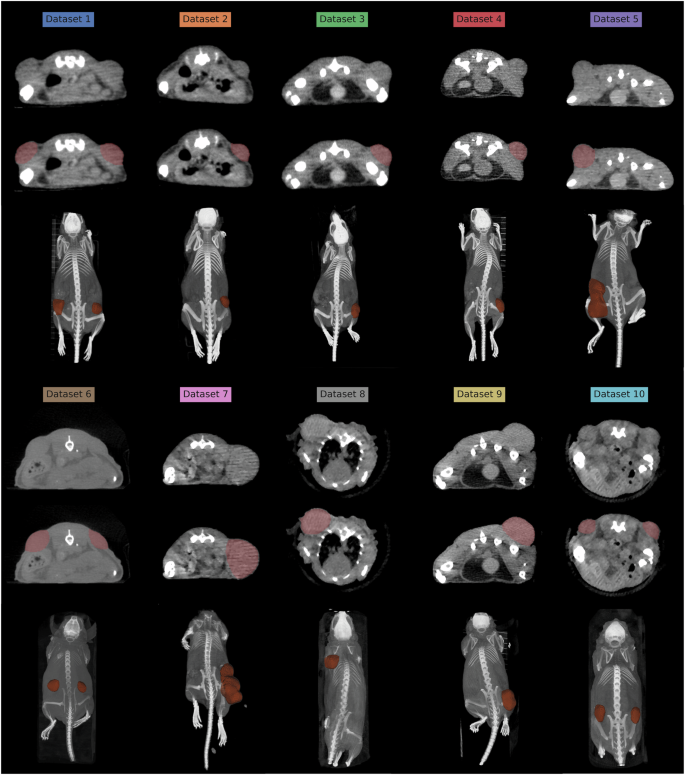

Ten µCT datasets from 2014 to 2020 were collected (Table 1 and Figure 1). All animal experiments were approved by the Danish Animal Experiments Inspectorate (permit number 2012-15-2934-00064 and 2016-15-0201-00920). The animals were housed in the core animal facilities at the University of Copenhagen, Denmark, where they were exposed to a 12:12 hours light/dark cycle, with a temperature of 21 ± 2 °C, and access to water and rodent food ad libitum. The animals were acclimatized for at least one week before being included in the experiments. The included µCT scans have not previously been published but were only used to anatomically guide the extraction of values from corresponding PET images.

The 10 datasets collectively contain 452 µCT scans of 223 individual mice. The mice were scanned longitudinally at different time intervals on a preclinical µCT/PET scanner (Inveon, Siemens, USA). All scans were performed on athymic nude mice with human xenografted tumor cells, which had been allowed to develop into subcutaneous tumors prior to performing the scans. In 3 of the 10 datasets, each animal had two tumors: one on each flank. In the remainder of the 7 datasets, each animal had one tumor on the flank (Table 1 and Figure 1). In Dataset 8, the mice had the tumor inoculated behind the front legs instead of the flank. Mice with external necrosis on tumors and a total tumor burden of over 2000 µL were euthanized due to ethical concerns, and a typical humane endpoint would be 1500 µL. In Dataset 8 and 10, the mice were scanned in a small animal bed, and the remainder of the mice were scanned laying freely on the bed, which reflects different real world scanning scenarios.